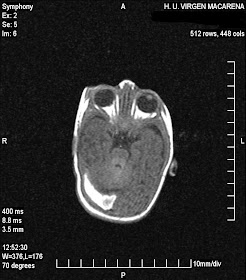

varón de 45 años que ingresa por cuadro de cefaleas y desorientación de 3 semanas de evolución